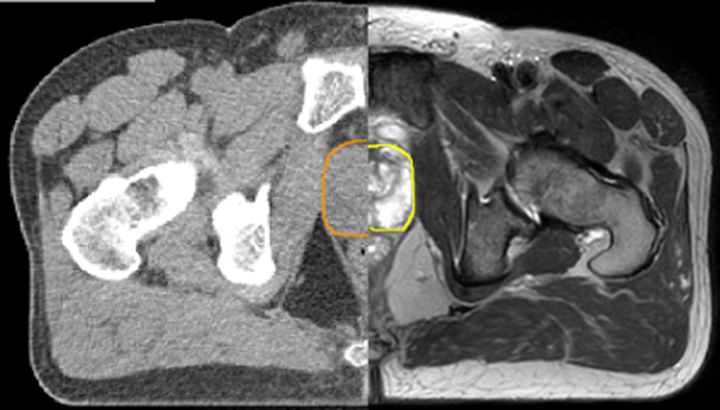

With its exceptional soft-tissue visualization capabilities and wide range of image contrasts, MRI has become a powerful tool to help more precisely define tumor boundaries. This is particularly important as it has been established that there is a high degree of uncertainty in target volume delineation, and it is even reported to represent the largest uncertainty in the entire radiotherapy process for most tumor sites**. Better visualization of the target area and nearby organs-at-risk is a key factor in enhancing target volume delineation. MRI’s expanding role also can be attributed to its functional imaging capabilities, which can inform both target characterization and treatment response.

With its superior soft tissue contrast compared to CT, MRI offers exquisite visualization of tumor boundaries and proximity to nearby critical structures.

The ability to tune contrasts can provide even more valuable information about tumor characteristics and tumor extent to facilitate enhanced delineation, and also provides possibilities for dose boosting strategies.